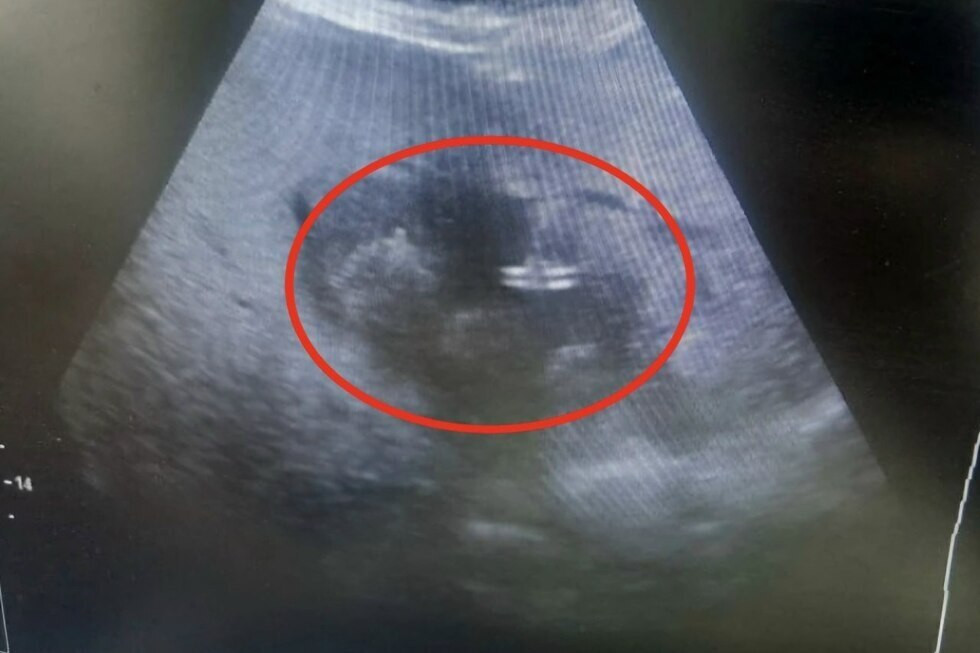

Врачи отметили, что учитывая преклонный возраст пациентки и сопутствующие риски, традиционное полостное оперативное вмешательство могло быть опасным. Вместо этого было выполнено малоинвазивное дренирование абсцесса печени под контролем ультразвуковой навигации, что позволило минимизировать травматизацию тканей и ускорить восстановление.